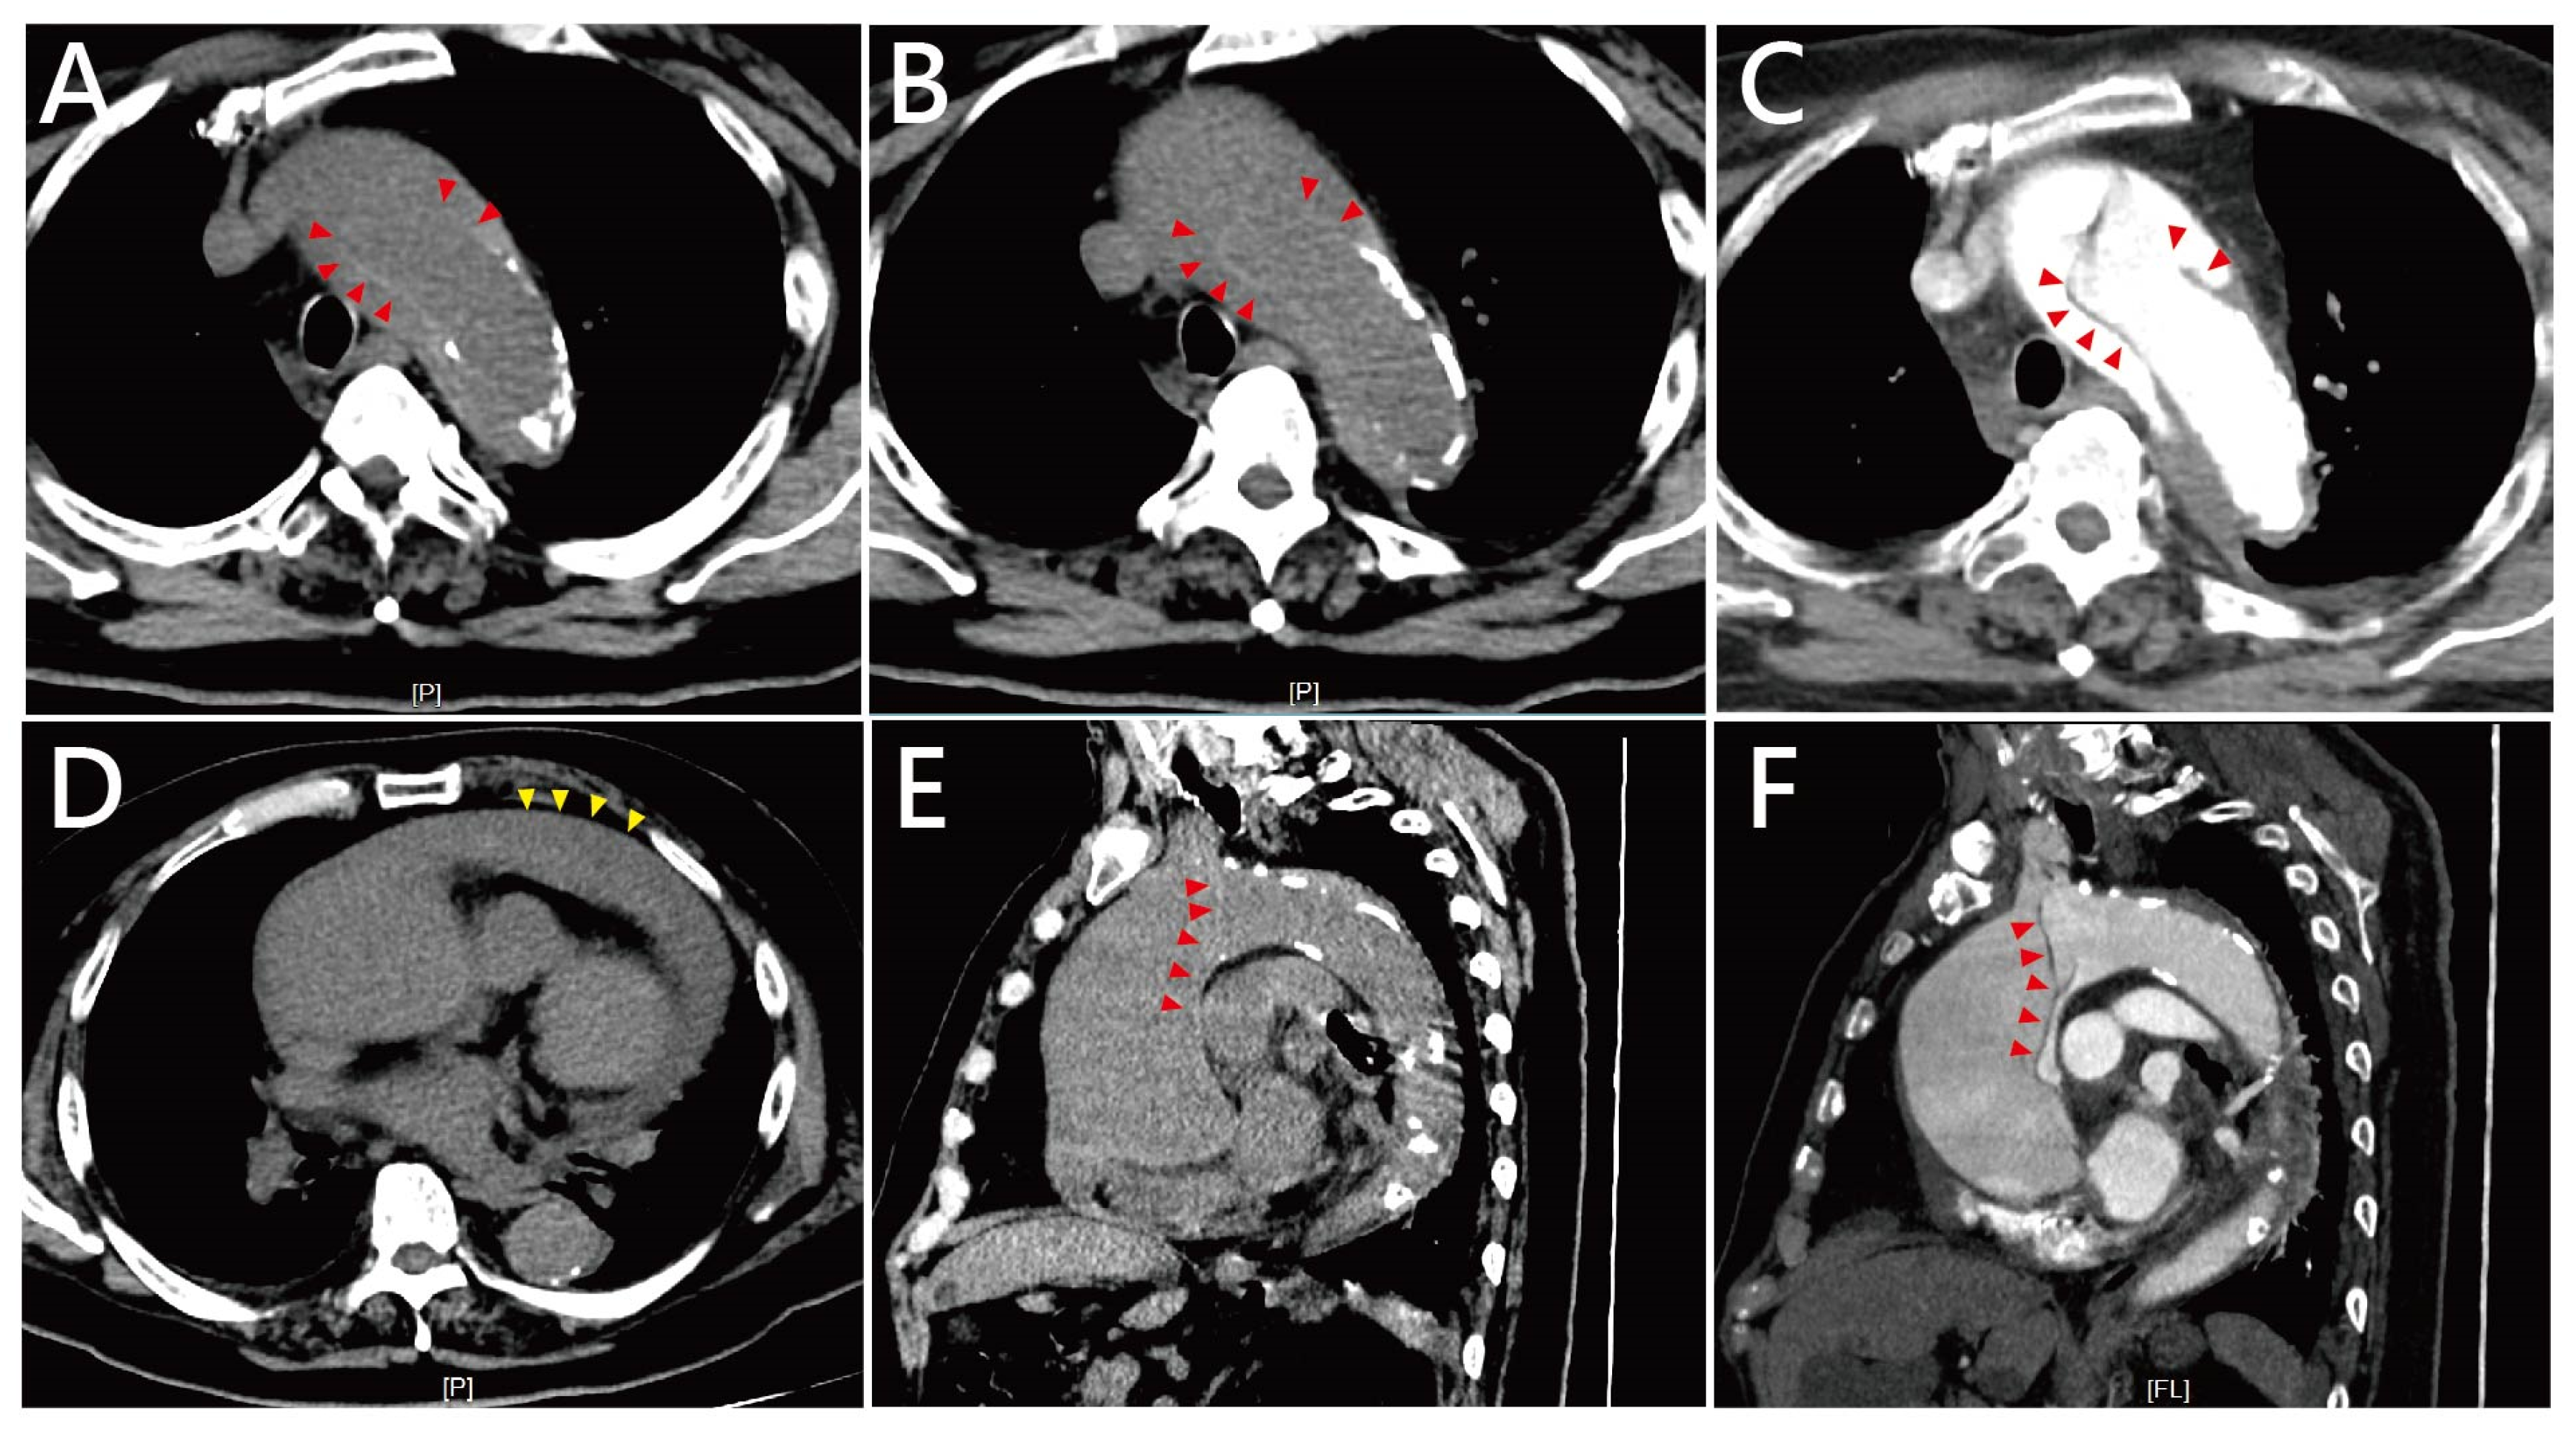

2. Case Presentation